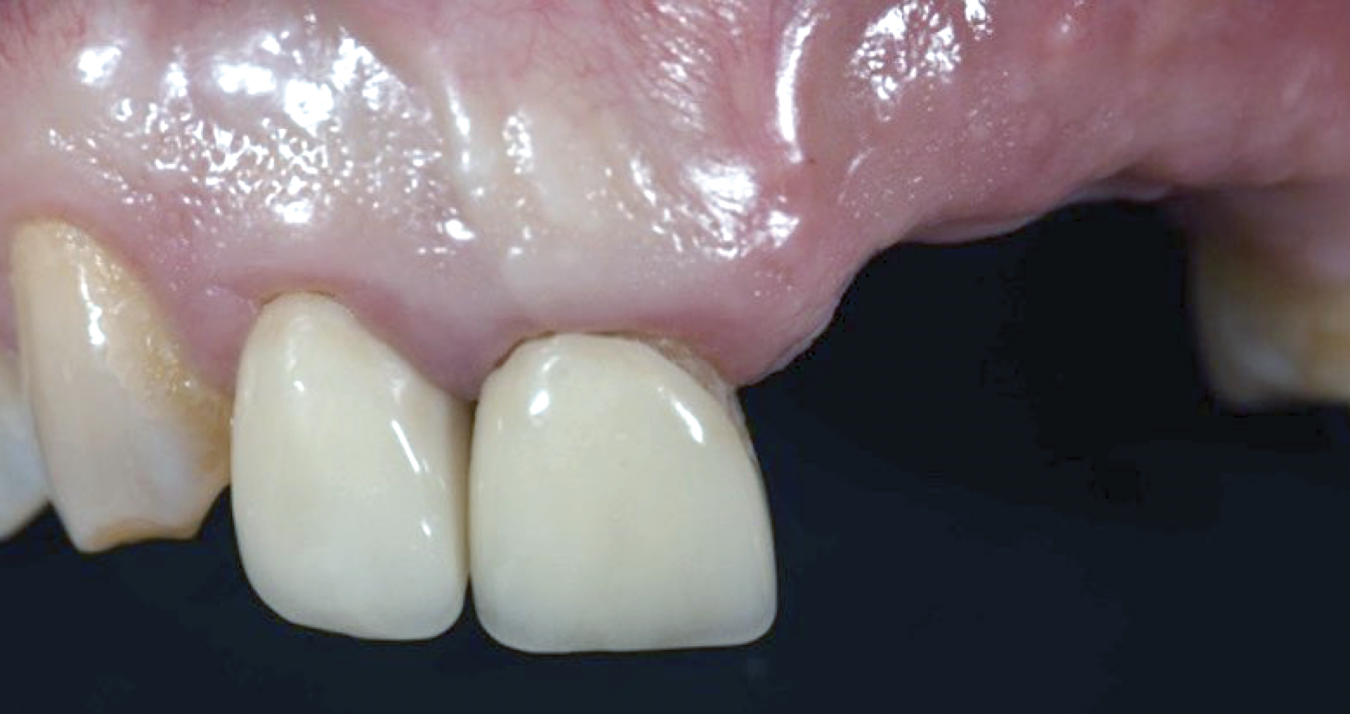

After 3 months of healing, the second-stage procedure was performed to uncover the dental implants. Then, after 6 months of soft-tissue conditioning with temporary crowns, the case was completed with permanent, implant-supported restorations (Figure 16 and Figure 17).

Fig 16. Final clinical outcome at 12 months post–iCTG augmentation.

Figure 16